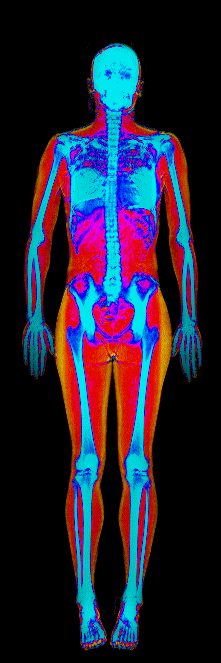

A DEXA scan passes two low-dose X-ray beams through your entire body, head to toe. Different tissues absorb different amounts of energy: bone absorbs the most, muscle and lean tissue less, and fat the least. The scanner reads how much energy made it through every pixel and assigns each one to a tissue type.

The colorful image at the top of every BodyStats DEXA report is literally that map. Bone shows up in cyan and white. Lean tissue is red. Fat is yellow and orange. Your body-fat percentage isn’t an inference — it’s a count of how much of that image is yellow and orange, broken out region by region: left arm vs right, left leg vs right, trunk, android (belly), gynoid (hips). And visceral fat — the dangerous abdominal fat that bioimpedance can’t see at all — comes back as its own number in cm².

This page features real, anonymized DEXA scan images from BodyStats clients, organized by gender and body fat percentage in 5% increments. DEXA (Dual-Energy X-ray Absorptiometry) is the clinical gold standard for measuring body composition — far more accurate than scales, calipers, or visual estimates.

Each colorized scan shows the distribution of fat tissue (shown in warmer colors) and lean tissue (cooler colors) throughout the body. Compare your own DEXA scan to others in your range, or see what different body fat levels actually look like on a scan.

Female DEXA Scans by Body Fat %

15 to 20% body fat